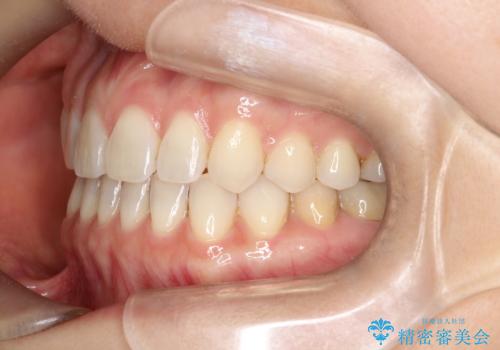

【インビザラインで再矯正】マウスピース矯正で隙間を閉じたい

- 過去に矯正を行ったあと、前歯の後戻りを主訴に来院されました。

マウスピース矯正にて隙間を閉じる計画をたて、治療を行いました。